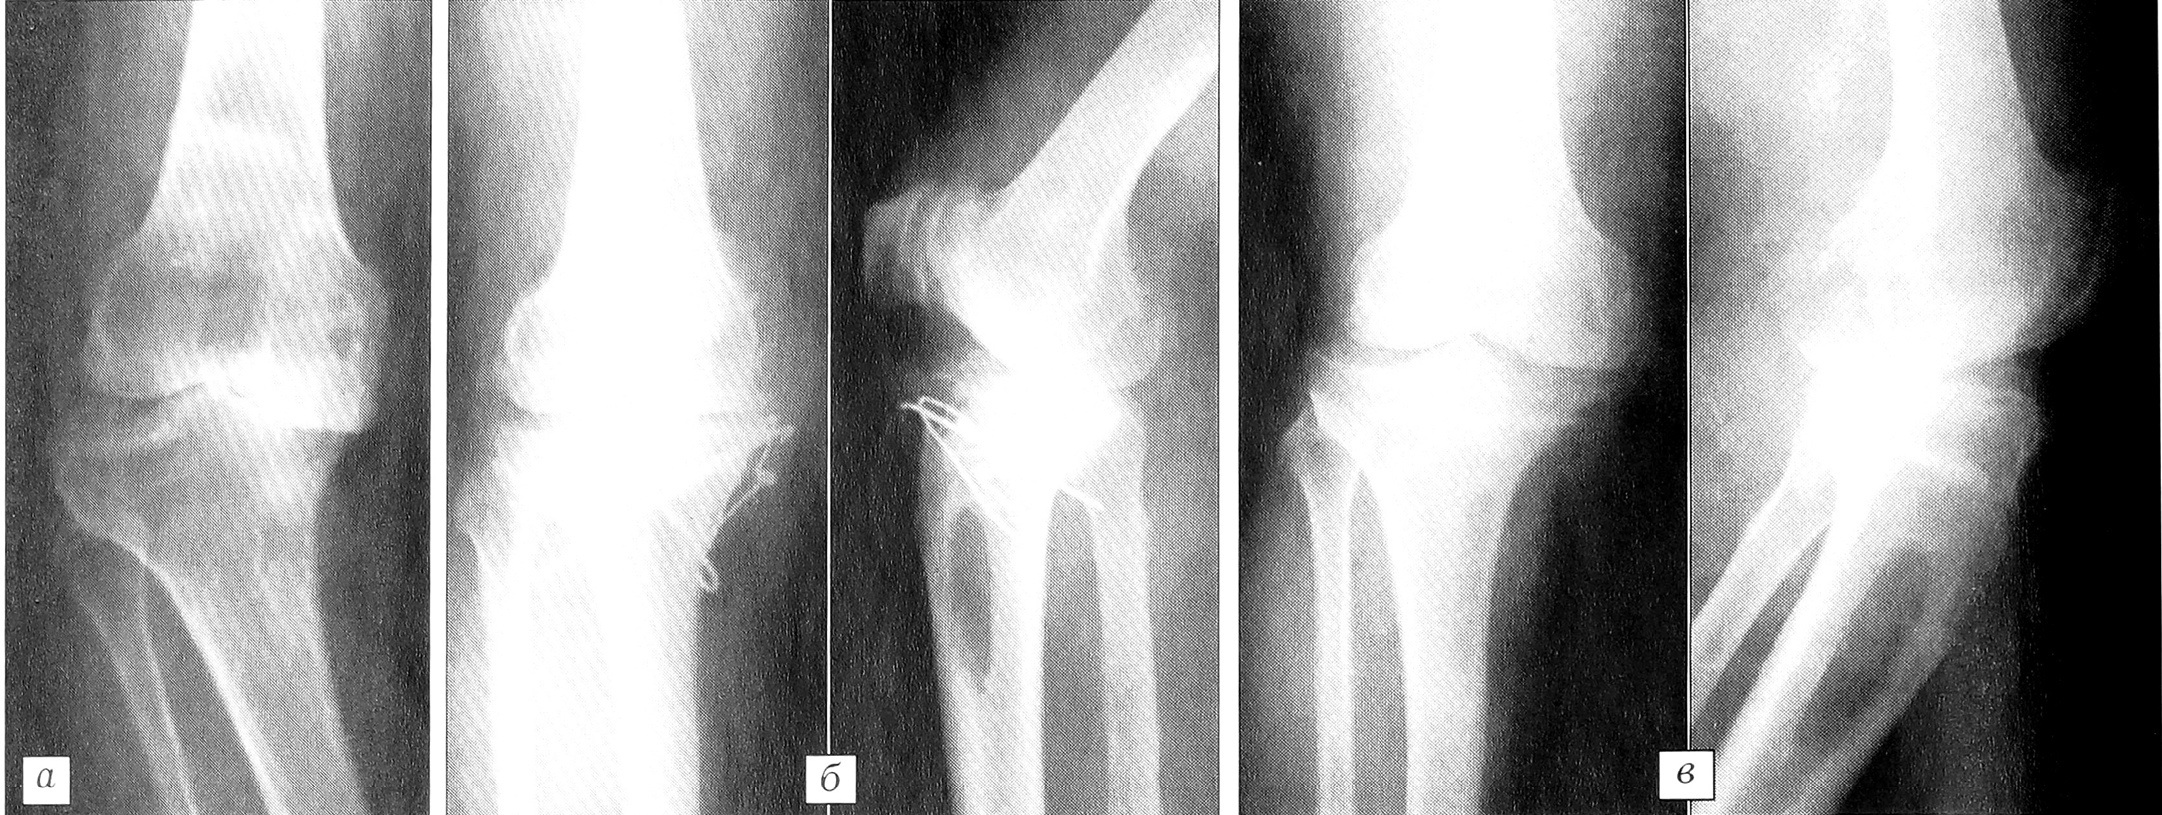

Рис. 2. Рентгенограммы правого коленного сустава больной К.a — до операции; б — непосредственно после операции; в — через 7 мес после операции.

16.06.00 произведена вальгизирующая клиновидная остеотомия правой большеберцовой кости с костной пластикой дефекта аутотрансплантатом на питающей ножке, пластика наружной боковой связки местными тканями. Гипсовая иммобилизация продолжалась 4 нед, нагрузка на ногу разрешена на 9-й неделе (рис. 2).

Наблюдение за больной с использованием балльной скрининговой системы контроля показало стойкое снижение тяжести заболевания с 31 (декомпенсированная форма) до 18 (субкомпенсированная форма) баллов (рис. 3). Объективным подтверждением исчезновения болевого эндостального синдрома явилось снижение ВКД с 2,8 кПа перед операцией до 0,8 кПа через 1,5 года после оперативного лечения.